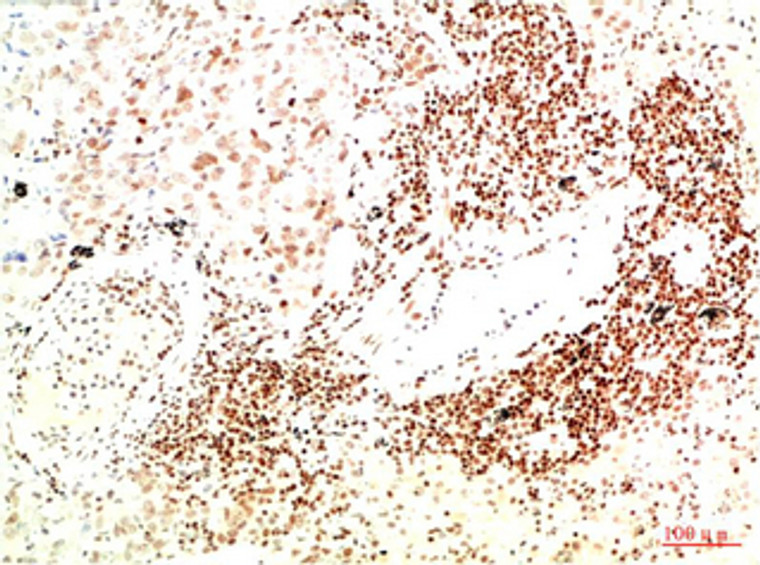

IHC/IF |

Mouse monoclonal antibody anti-Tyrosine-protein kinase JAK2 is suitable for use in Immunohistochemistry and Immunofluorescence research applications. |

IHC-P 1:50-300IF 1:50-200 |

The antibody detects endogenous JAK2 protein |